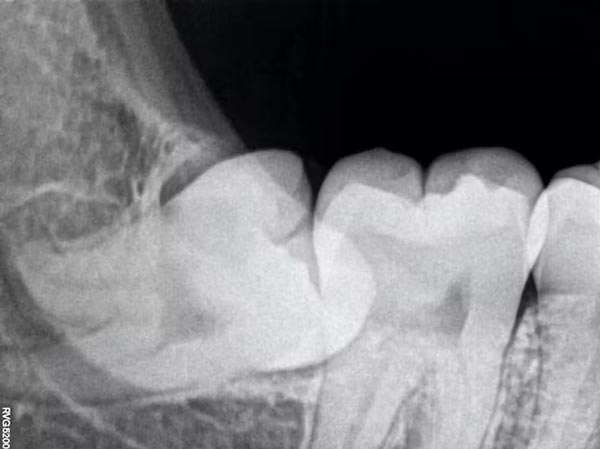

Às vezes, devido à falta de espaço, os dentes do siso podem ficar presos dentro do osso maxilar e nunca aparecem totalmente – ou eles emergem apenas parcialmente.

O chamado dente do siso impactado acontece com mais frequência na mandíbula inferior do que na mandíbula superior. Nos casos em que os dentes do siso estão apenas parcialmente para cima, as pessoas às vezes podem sentir dor, cárie dentária ou inflamação da gengiva, e é por isso que eles acabam tendo que ser arrancados.

Mas os dentes do siso geralmente não precisam ser removidos se estiverem totalmente erupcionados na boca, posicionados corretamente e saudáveis. Os dentistas podem examinar sua boca para ver se seus dentes do siso estão presentes, ou olhar para imagens de raios-X de sua mandíbula se esses últimos molares ainda não emergiram e você suspeita que eles podem estar afetados.